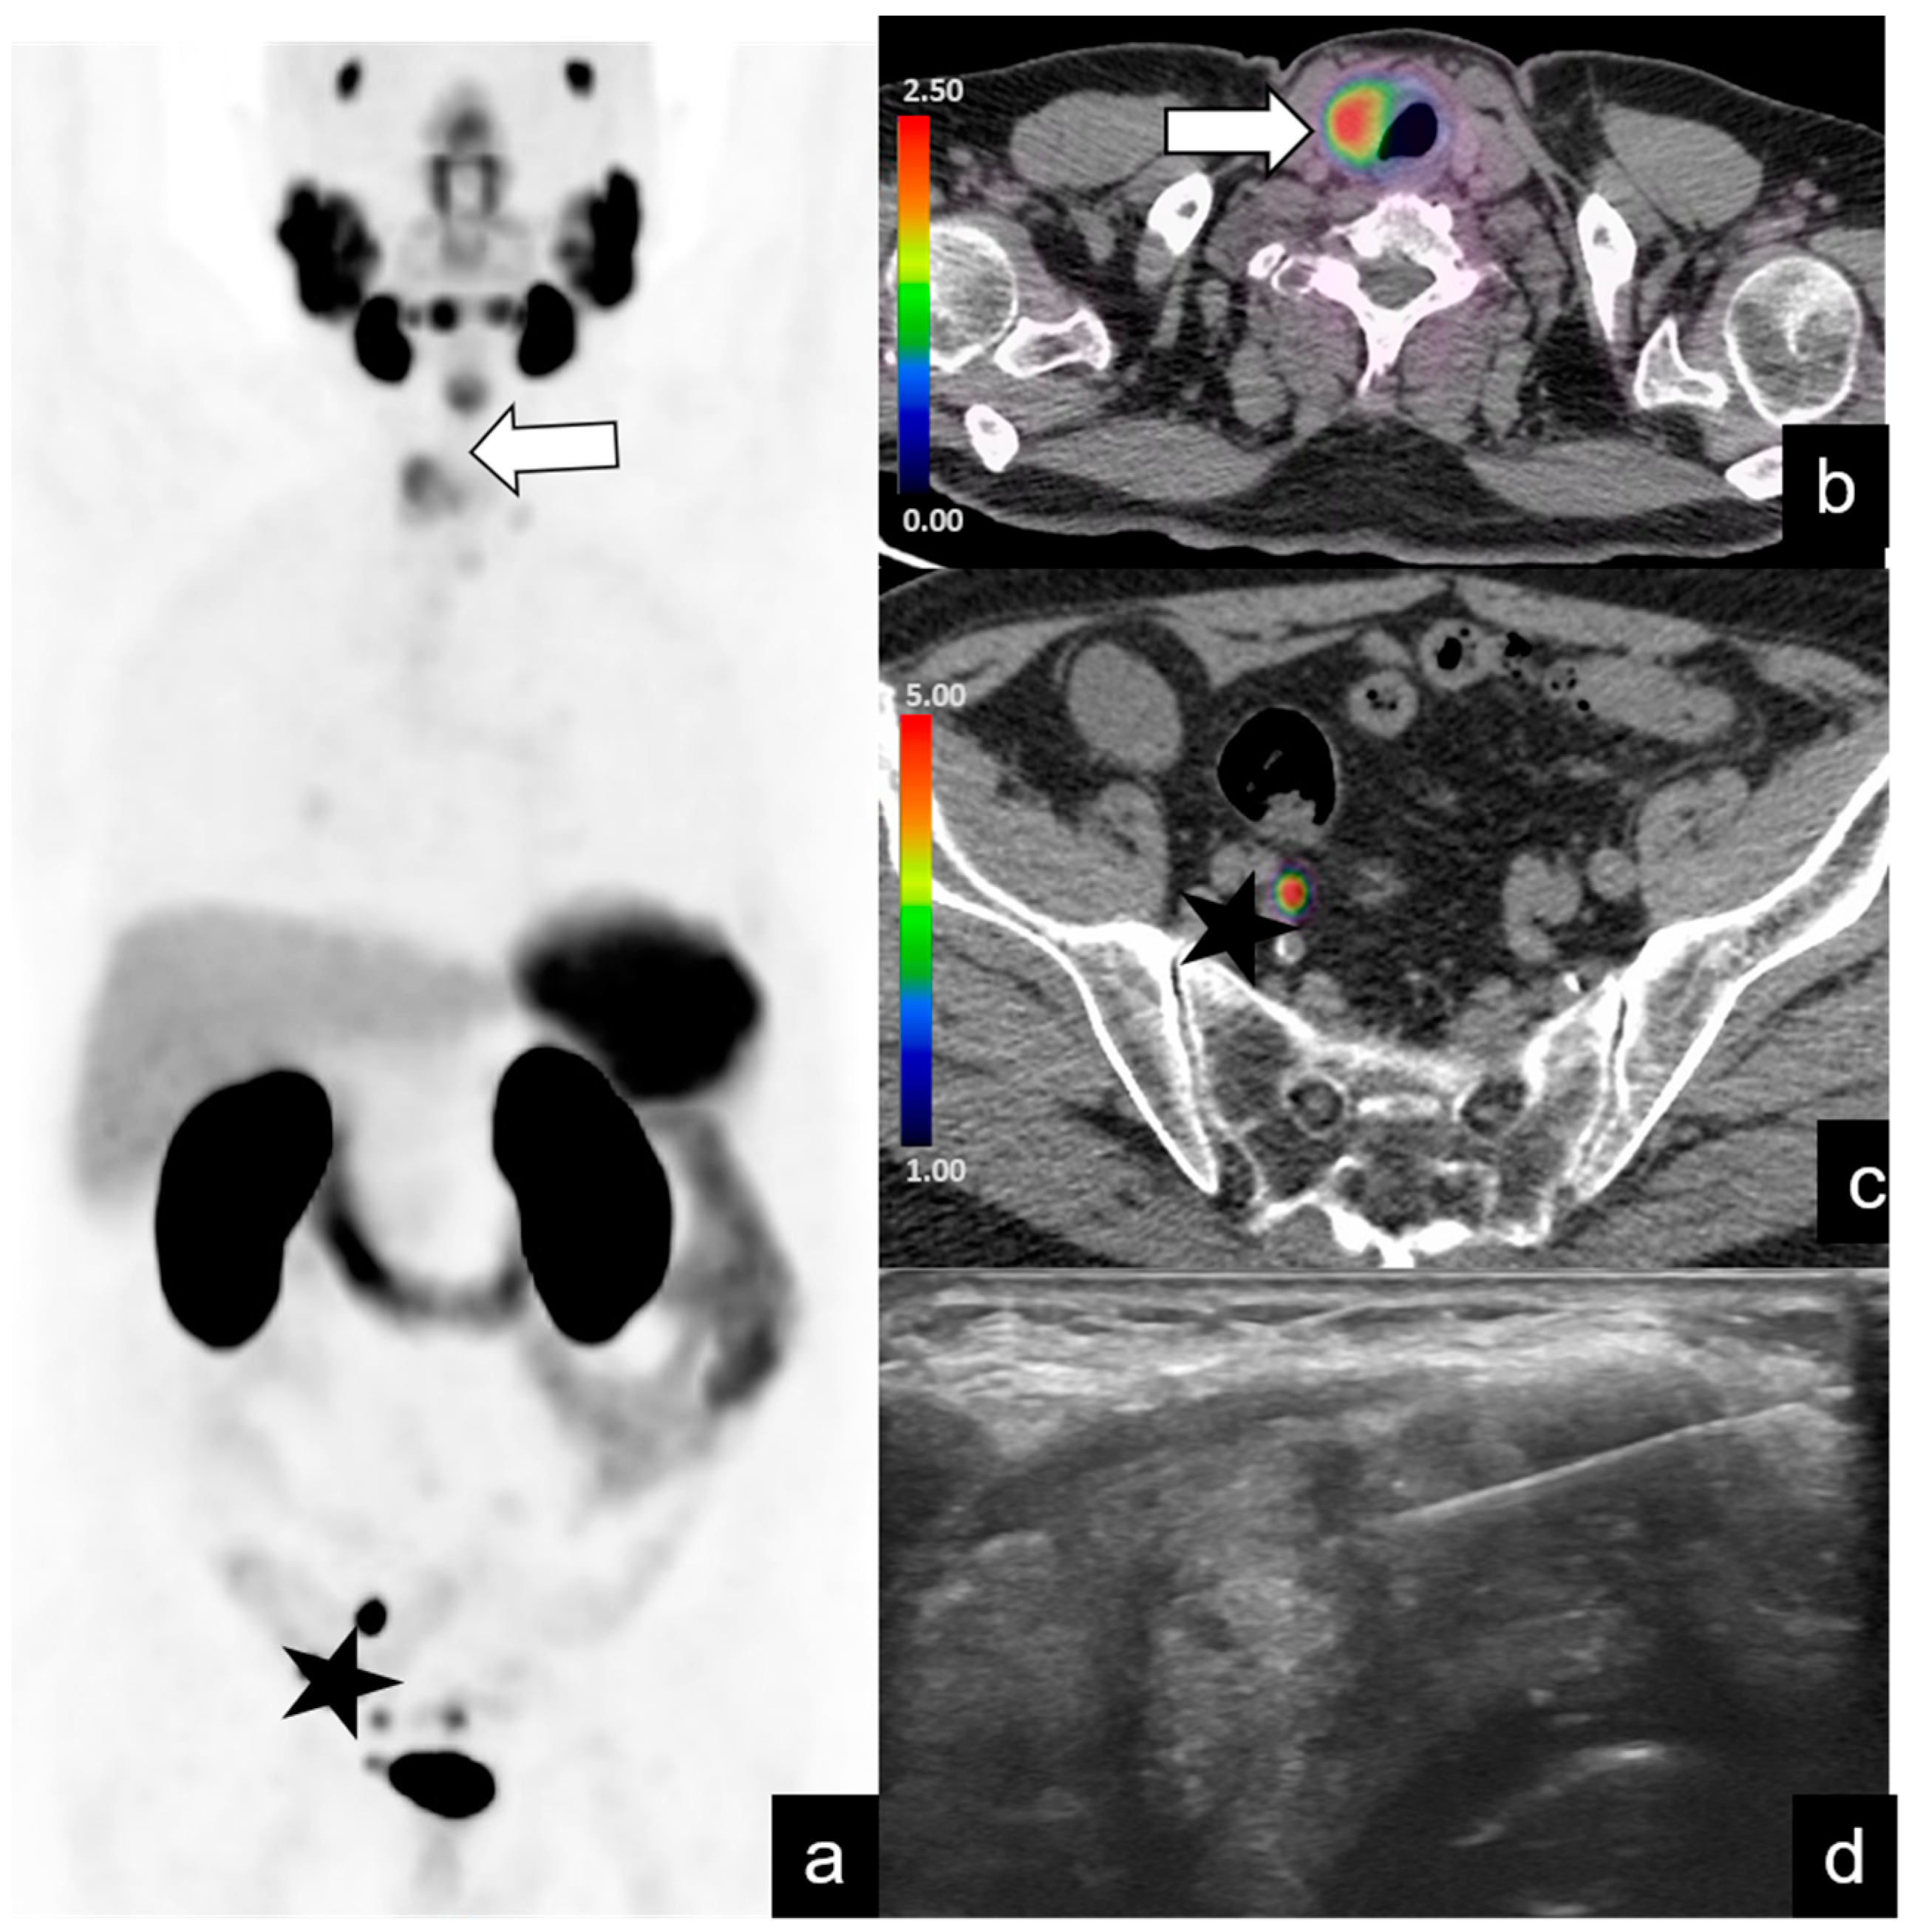

| Abdominopelvic | 39/128 (30%) | 24 | 1–73 | 7.3 | 2–19 |

| Supradiaphragmatic | 4/128 (3%) | 27.2 | 3–60 | 18.5 | 15–22 |

| Bone metastases | 20/128 (15%) | 19 | 1.9–70 | ||